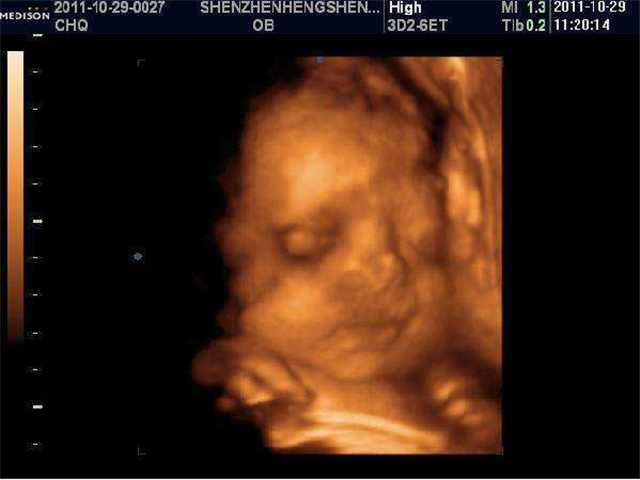

小丽和她老公是奉子成婚。在怀孕6个月时,也就24周的时候,小丽和她老公去到之前预约好的医院做四维彩超,可结果出来后,医生告知她们肚子里的孩子是畸形。